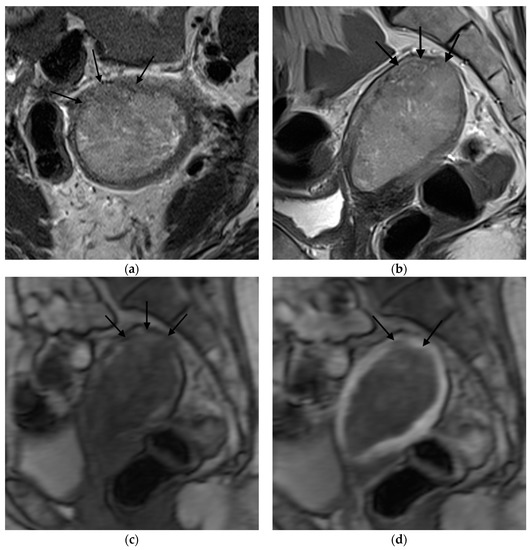

Figure 4. Representative MRI images of endometrial carcinoma of a false-positive case in a 67-year-old postmenopausal woman. (a) Sagittal T2WI MRI image shows a slightly hyperintense lesion with disruption of the junctional zone (arrow). (b) DCE-MRI image shows a hypointense lesion with thinning of the myometrium and ≥50% myometrial invasion. Subendometrial enhancement was not visible. However, the histopathological result revealed <50% myometrial invasion.